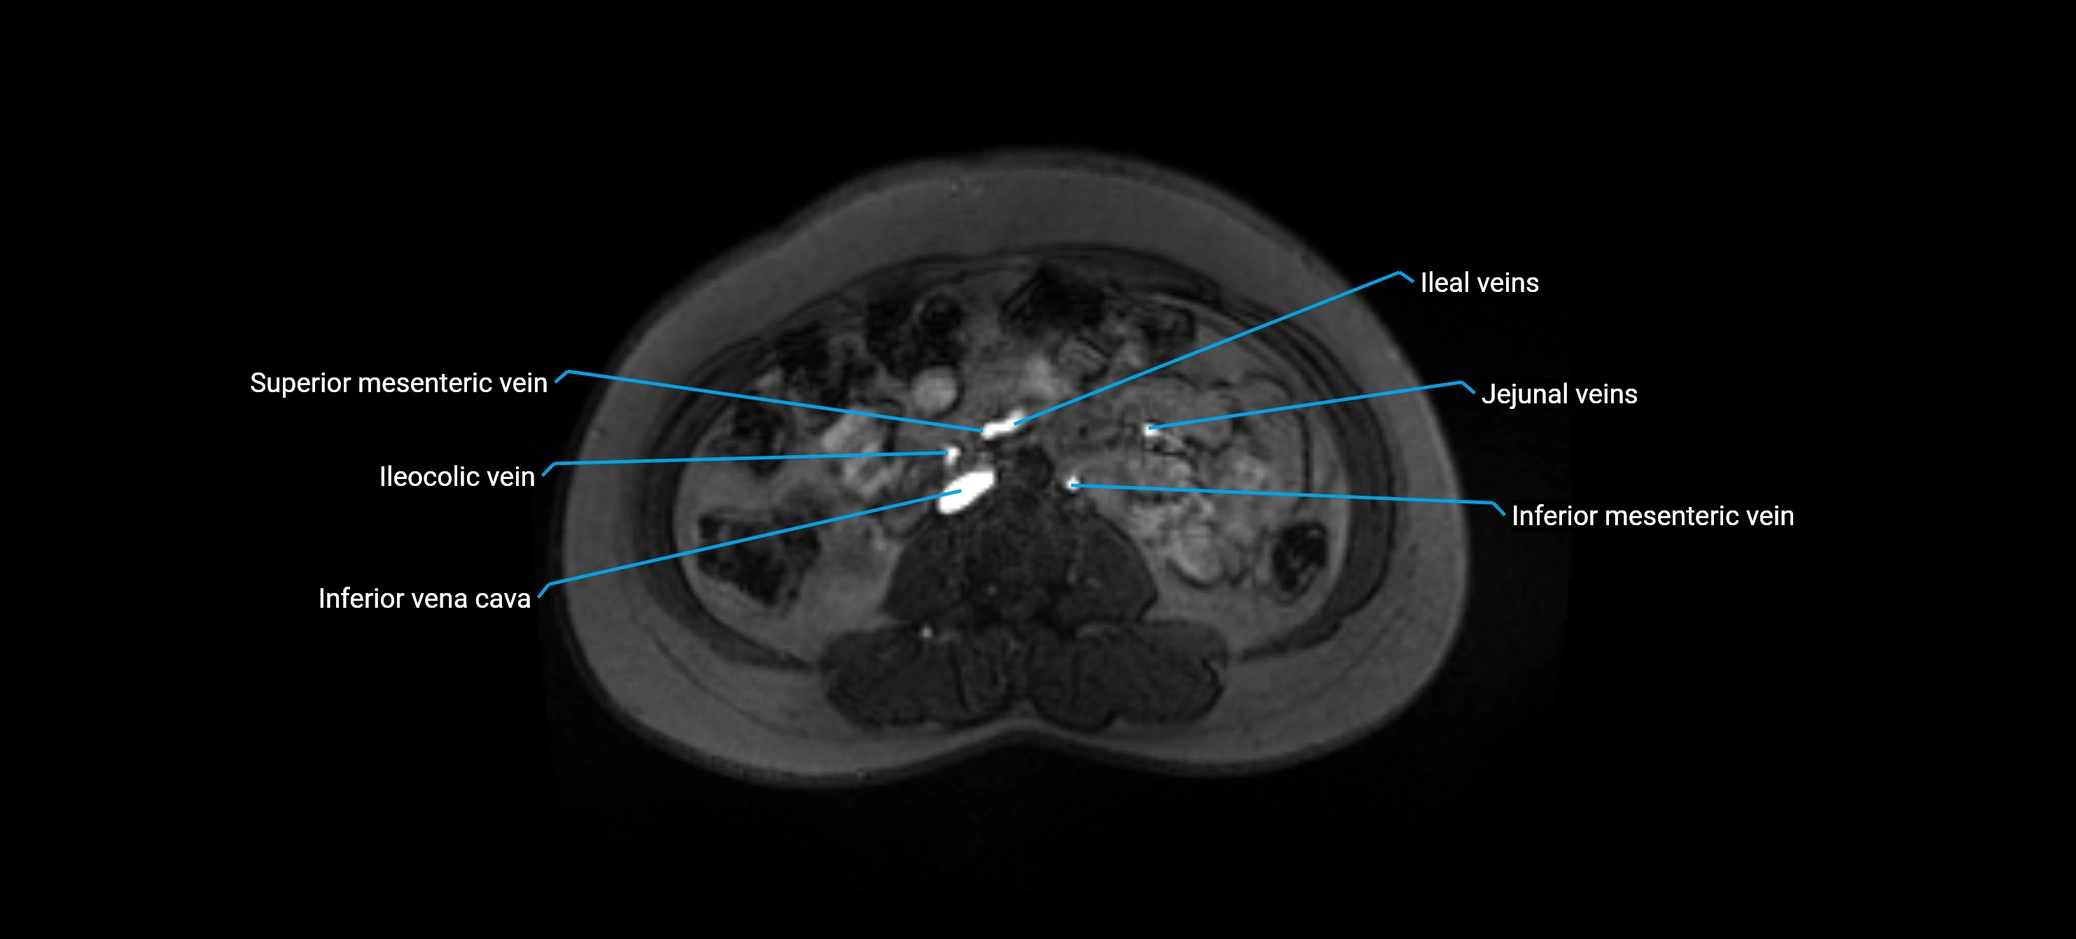

MRI image

image